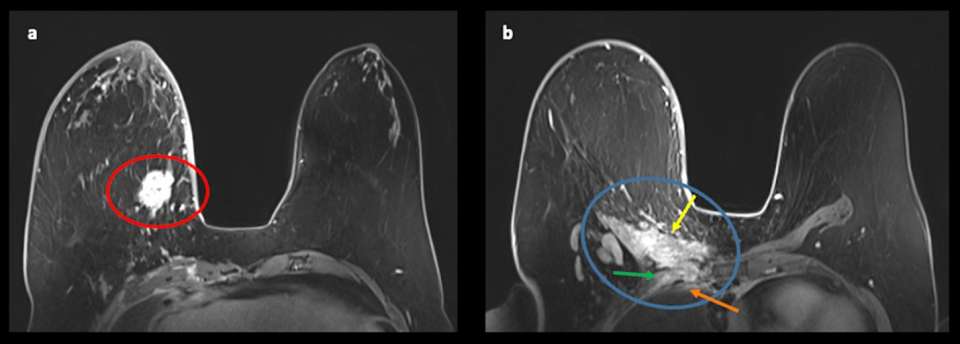

Case: Chest Wall Invasion Figure 1

Figure 1: Bilateral breast MRI, T1 sequence illustrating chest wall anatomy. The chest wall includes the sternum, ribs, intercostal muscles and serratus anterior (yellow arrows).